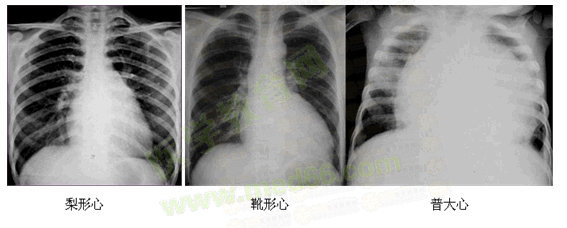

心臟大小

心臟